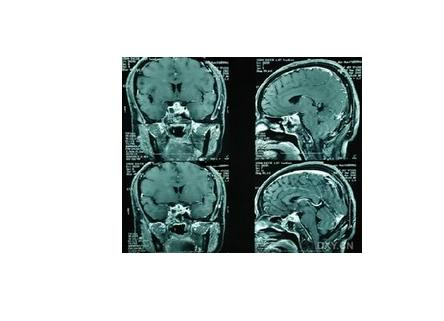

颅内感染是一种常见中枢神经系统疾病,是指由各种病原体感染脑实质、脑膜等引起的中枢神经功能障碍,常见的疾病有脑炎、脑膜炎、脑脓肿等。常由细菌、病毒、真菌、结核、螺旋体、立克次体或寄生虫等病原体感染引起。颅内感染的主要表现为发热、头痛、呕吐、癫痫发作、精神症状、意识障碍、惊厥、昏迷等。颅内感染的治疗方法有药物治疗、手术治疗。如不及时治疗,本病可能会引发梗阻性脑积水、昏迷颅内压增高、脑疝、休克、脑室炎、败血症等并发症。颅内感染的预后与病情严重程度、病原微生物种类、治疗时机、个人免疫、有无并发症等因素有关。化脓性脑膜炎病情凶险,病死率和病残率较高。脑炎轻症预后良好,少数患者可遗留癫痫、肢体瘫痪等后遗症。脑脓肿及时治疗,多数能治愈,但易遗留后遗症。